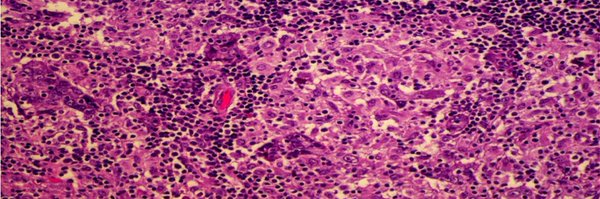

We are interested in the immune infiltrate in Breast cancer and what it means for treatment and prevention.

✨✨hot off the press from the #loilab. We show here that pregnancy & breastfeeding is associated with increased T cells in the normal breast and protection against #tnbc #breastcancer moving the role of immunity from treatment to prevention. 👏👏Thanks to @FAndreMD @DrChoueiri

Translational data shows that #breastfeeding helps personal immunity improving CD8+ T This work can help to understand better the immune system and breastfeeding mechanisms @LoiSher @OncoAlert #ESMO25 @FernandoOnco